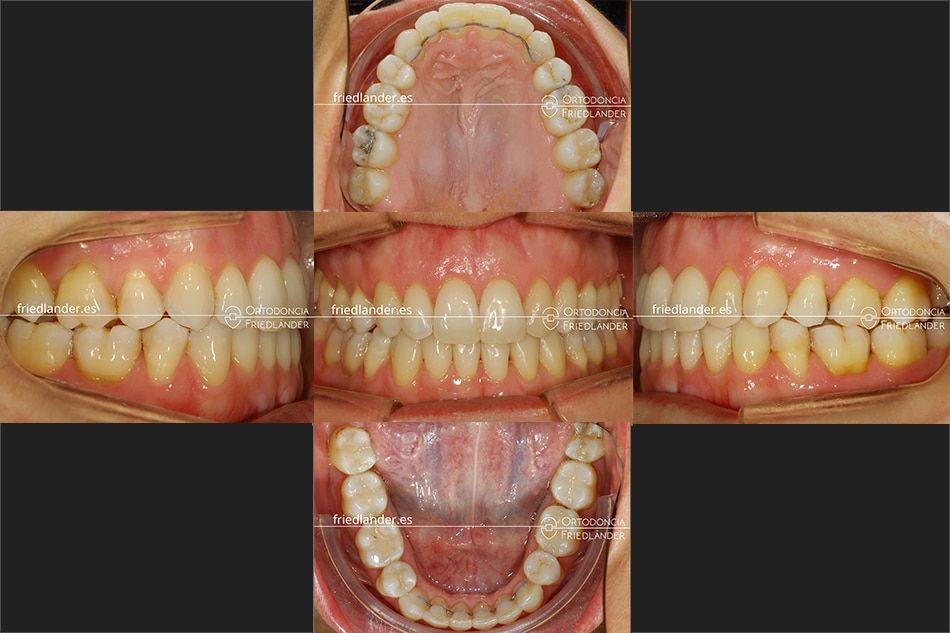

El tratamiento se realizó con distalización de la arcada superior, stripping y elásticos de clase II. En la siguiente imagen se puede ver el resultado a los 18 meses de tratamiento

En casos de pacientes adultos con apiañmiento anterior, al alinear los dientes, se suelen hacer evidentes unas troneras gingivales o «huecos negro en la encía» que se pueden solucionar con un correcto stripping.

Después de hacer stripping se elimina la tronera gingival marcada con una flecha amarilla.